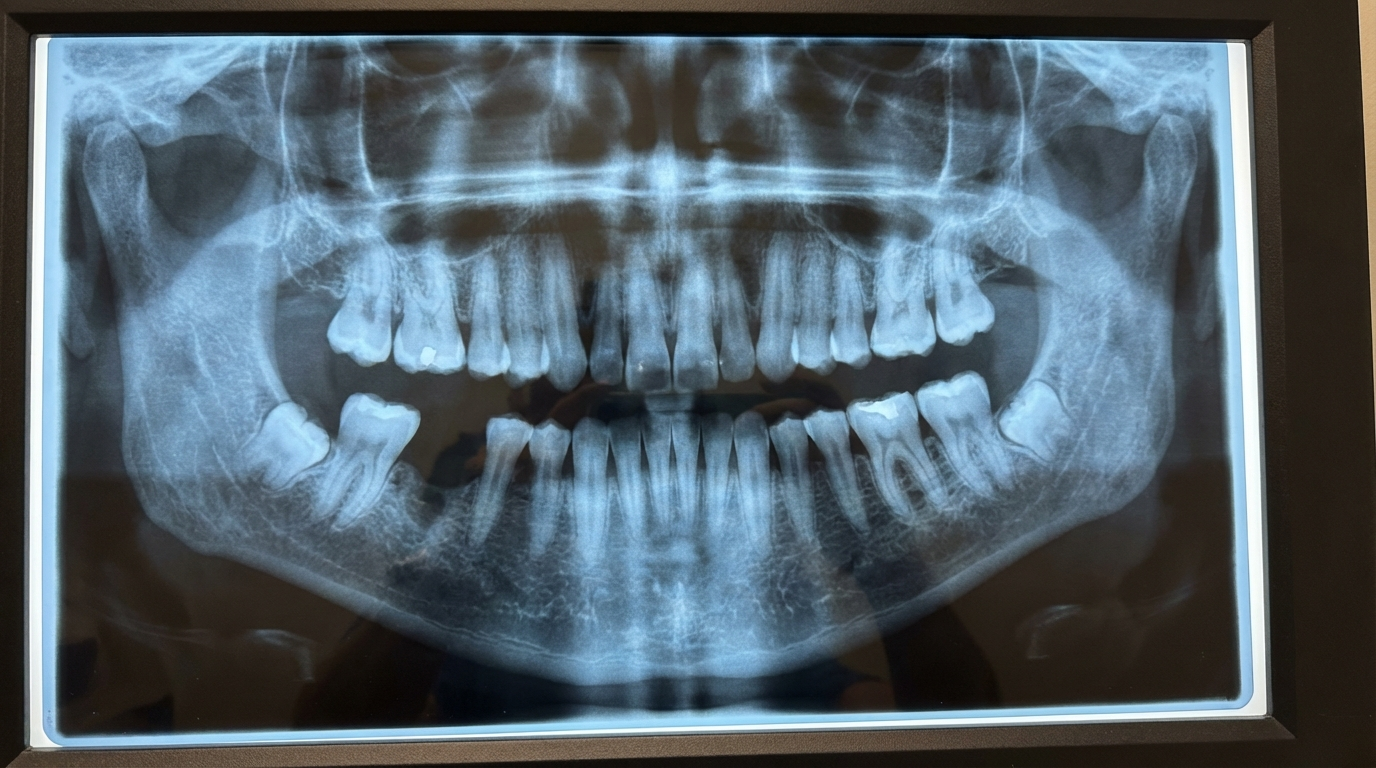

Stage 3: The Destruction. Pro-inflammatory cytokines begin destroying the connective tissue and the ligament holding your teeth in place. This is invisible. You can’t feel it. Your teeth still look normal.

Stage 4: The Bone Loss. The jawbone itself begins to dissolve. The foundation your teeth sit in is literally disappearing. Your gums pull away further. Your teeth start to shift. They look “longer.”

Stage 5: The Fall. Your teeth become mobile. They wobble when you press them with your tongue. And then one morning, eating toast, biting into an apple, sometimes doing nothing at all, a tooth comes out.